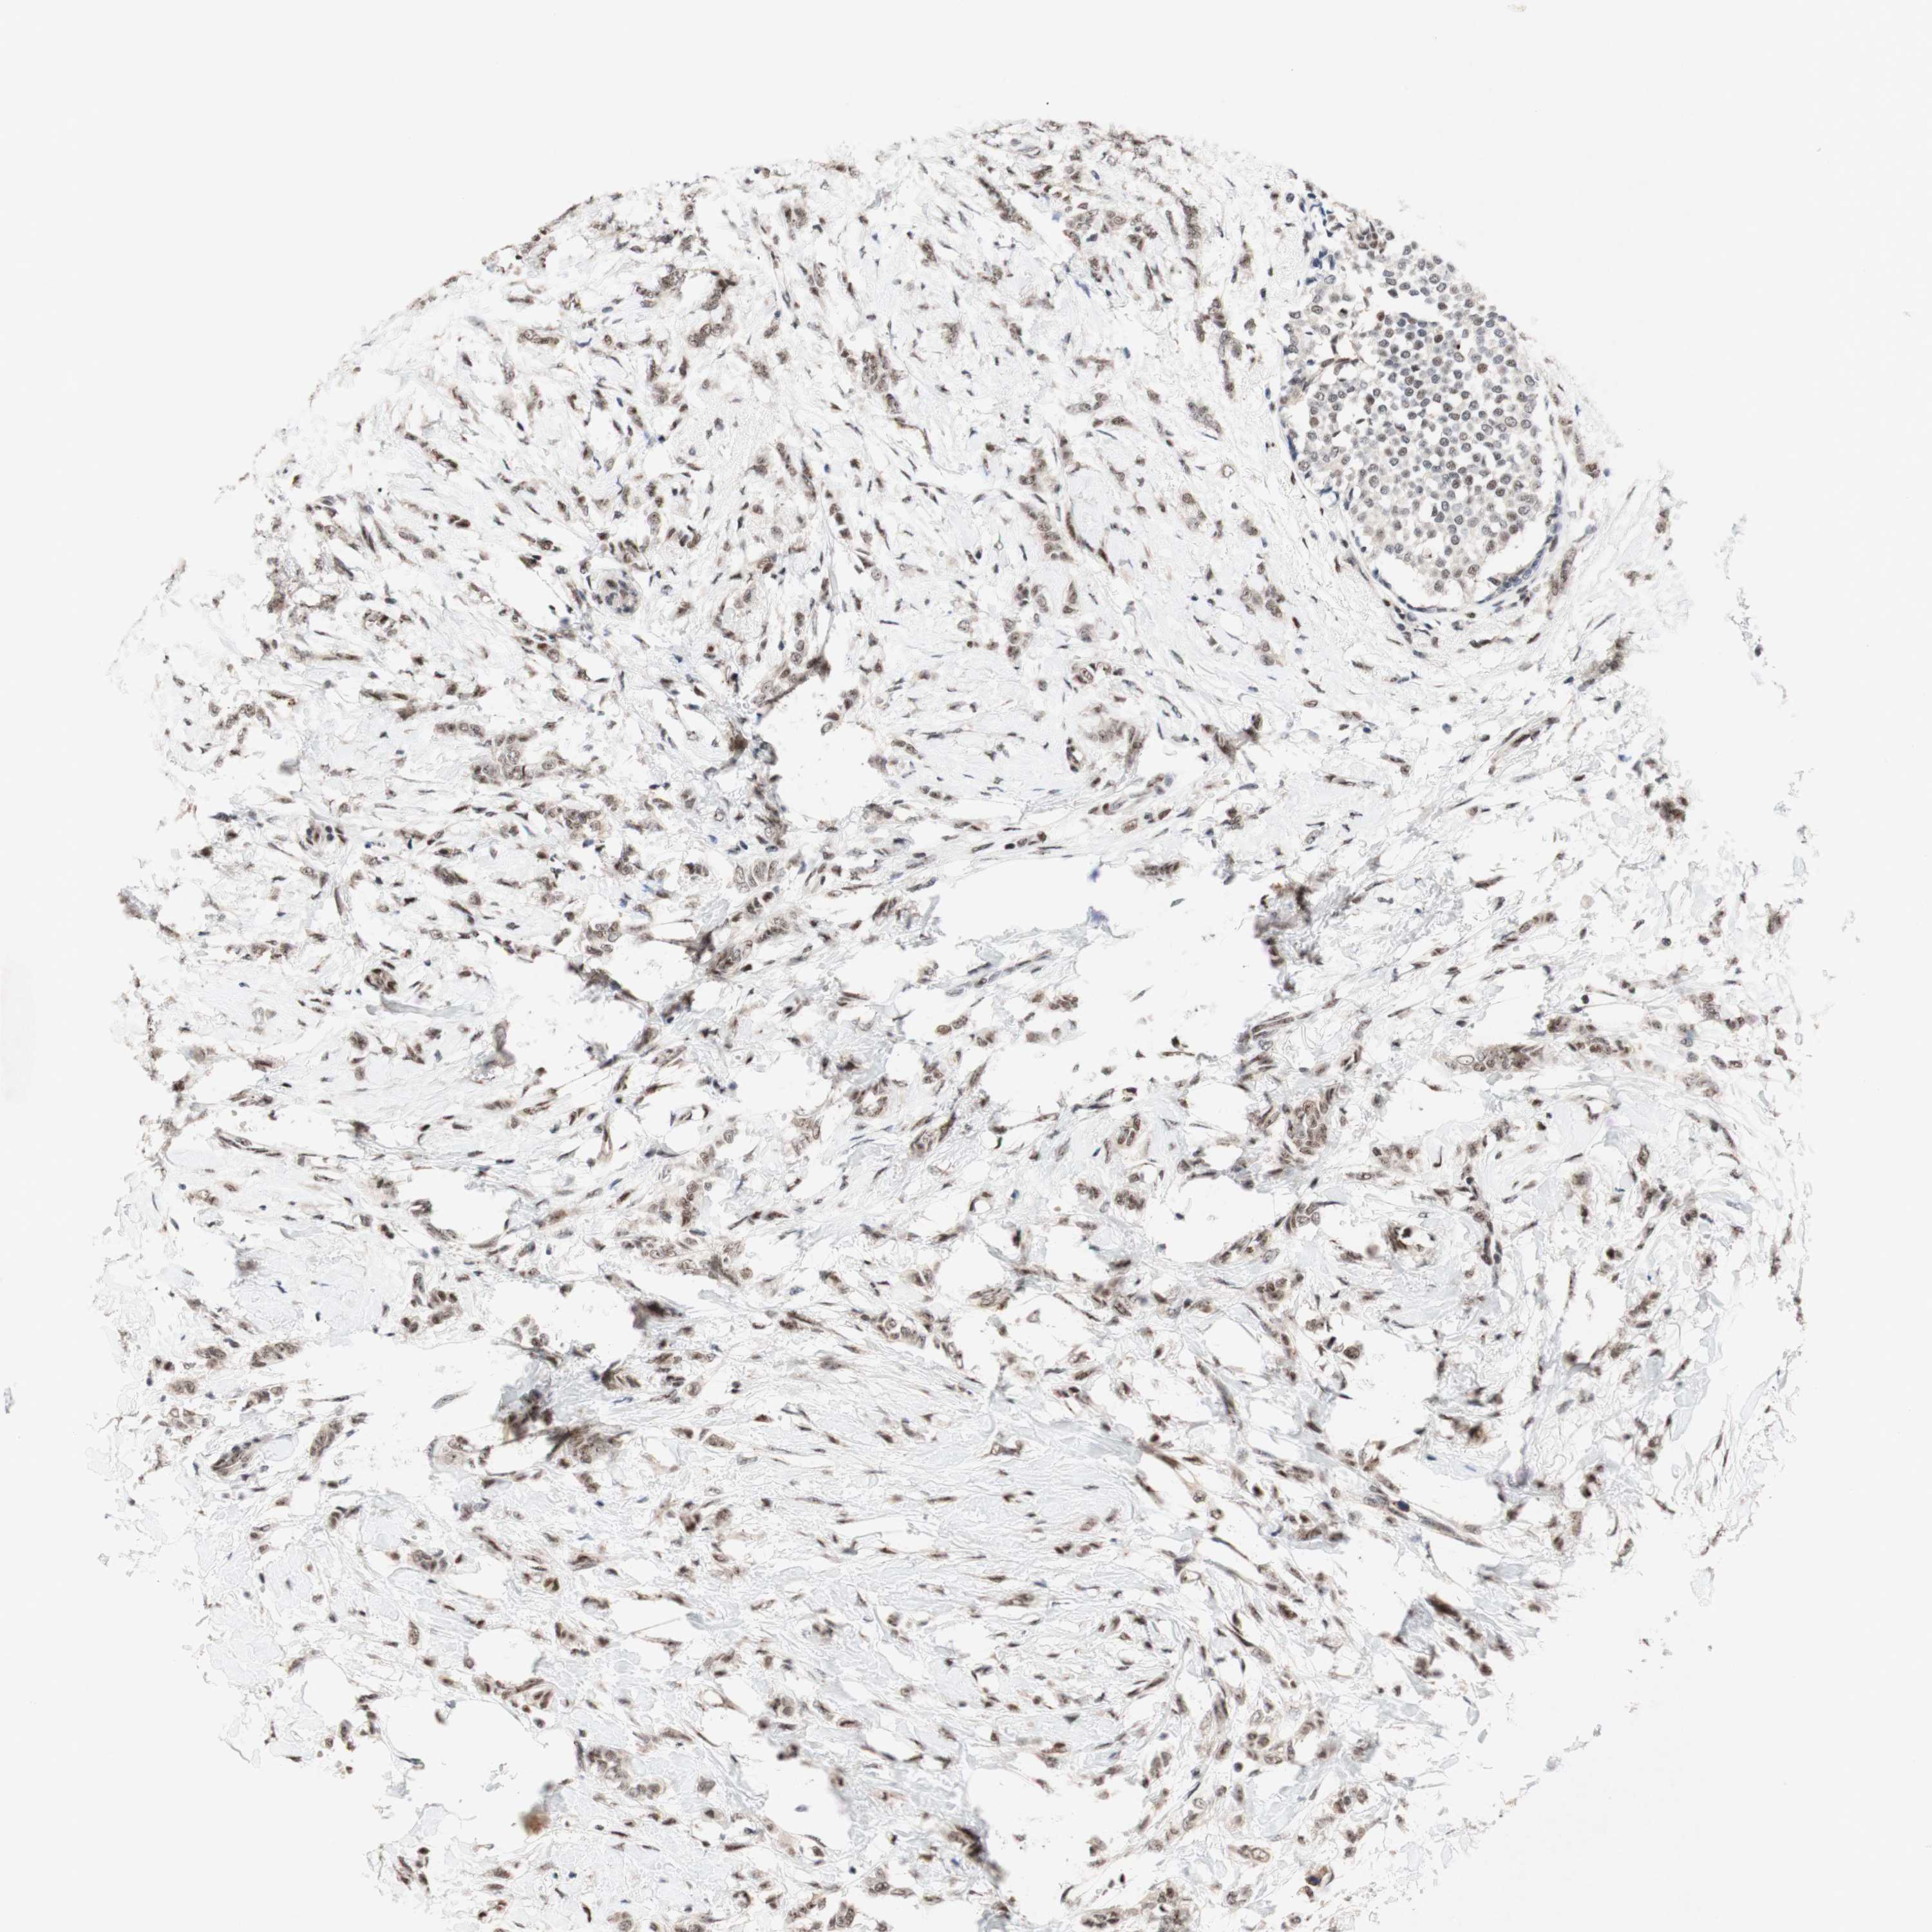

TLE1

CANCER BREAST CANCER Show tissue menu

BRCA TCGA BRCA VALIDATION PROTEIN EXPRESSION